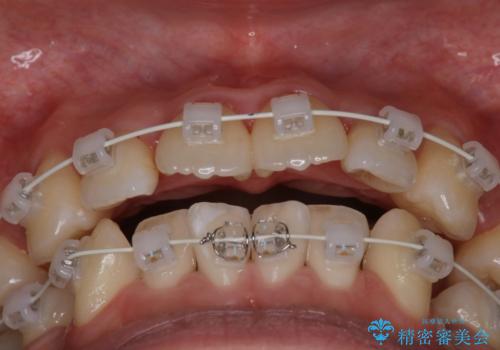

- 矯正装置

- 審美装置